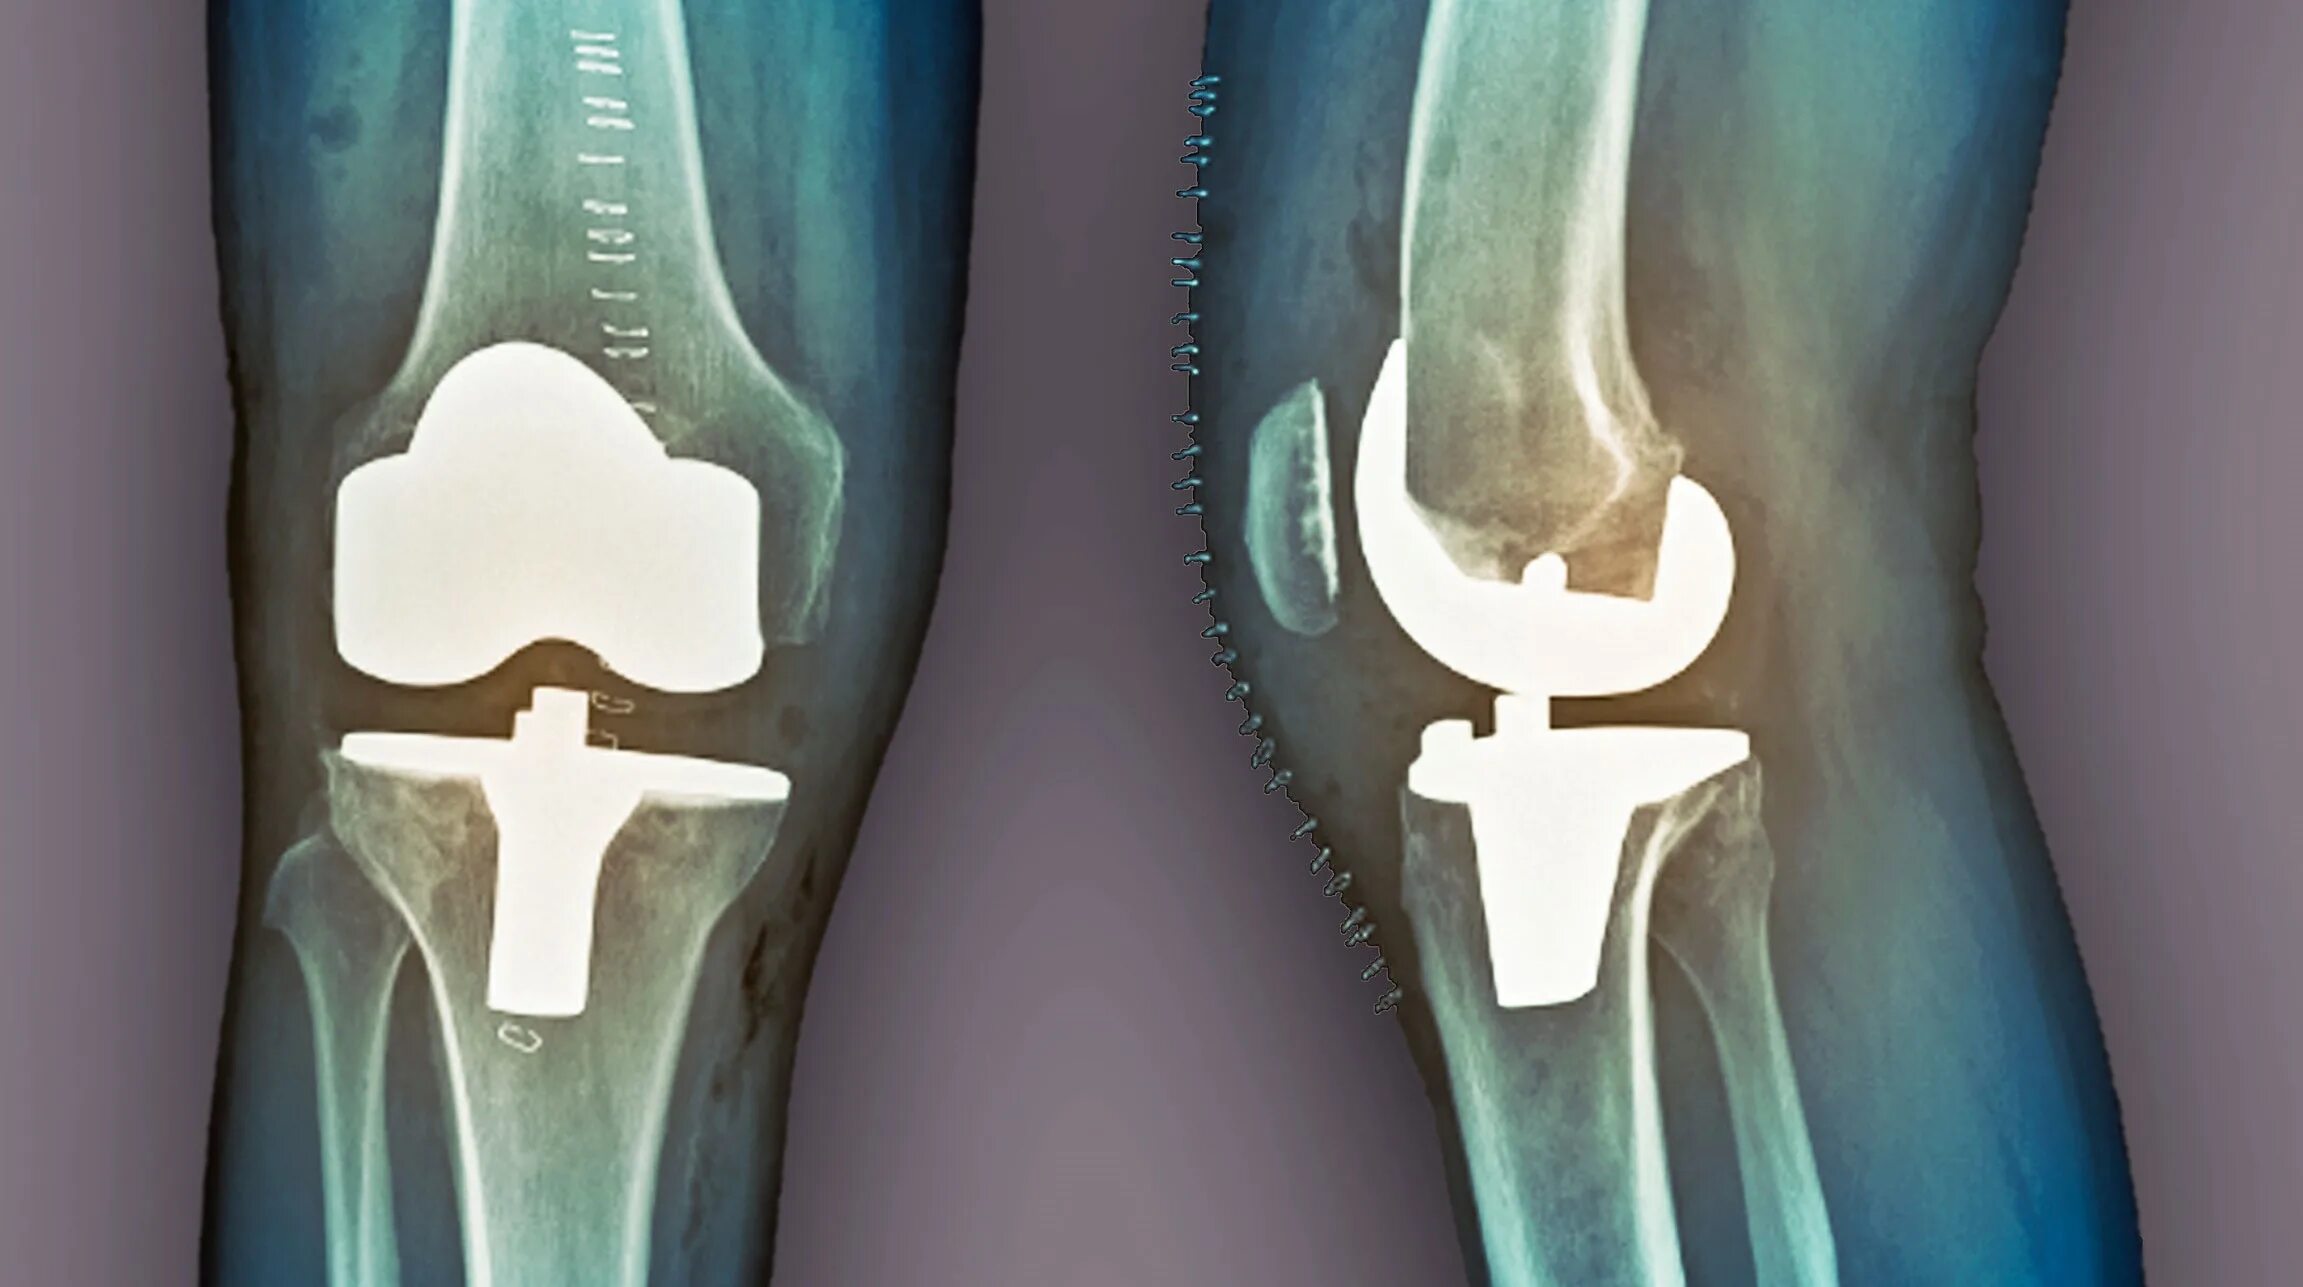

Артрит операции